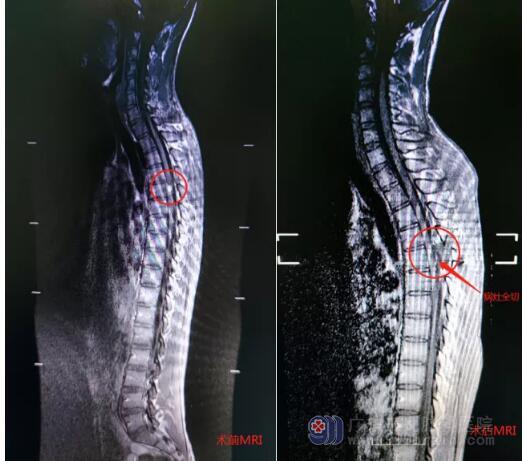

“肯定有问题,不能再拖了。” 李华思量后到学校附近医院就诊。检查后医生告知李华,他的胸段脊髓里面有个脊髓血管发育异常,可能是脊髓海绵状血管瘤并出血,手术风险大,术后下肢完全瘫痪的概率很高。

在科主任欧阳辉教授带领下,以毕中胜医师为主的脊髓脊柱团队经过精心准备,精准定位病灶,在显微镜下将肿瘤精准分离,顺利将生长于患者脊髓中央的海绵状血管瘤完整摘除,瘤体大小为10mm×8mm×8mm。

欧阳辉主任介绍,脊髓就像是“电话总机房出来的总电缆”,内含数万条细小的神经纤维。如果脊髓发生横贯性损伤,则患者会出现受损平面以下截瘫、大小便功能障碍及性功能障碍,这对于一个大三男生来说多难以接受啊。要在不到手指粗的脊髓中完整切除一个“血管瘤”,又不损伤脊髓是相当难的事情。为此,经充分的准备,借助先进的手术设备,确实为李华完整地切除了脊髓髓内血管瘤,且没有造成脊髓损伤,使他幸运成功的得到了康复。